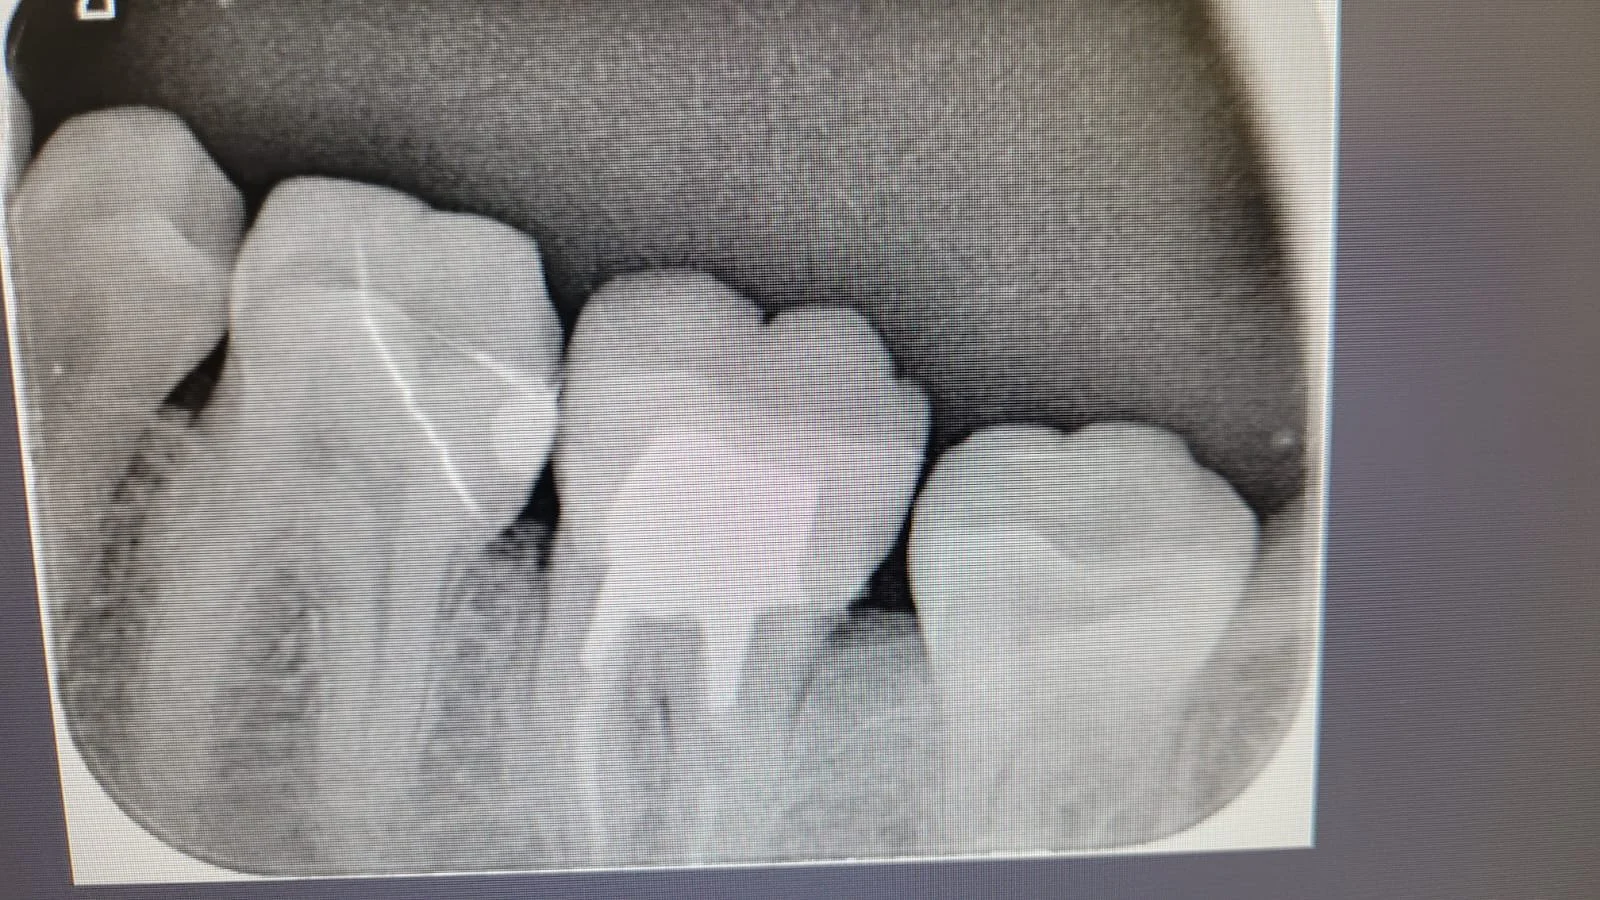

En la primera sesión realizaremos una evaluación integral de tu salud oral. Tomaremos radiografías y fotografías clínicas para analizar con detalle el estado de tus dientes y encías. También responderé tus dudas y te entregaré recomendaciones personalizadas para mantener una rutina de higiene oral efectiva.